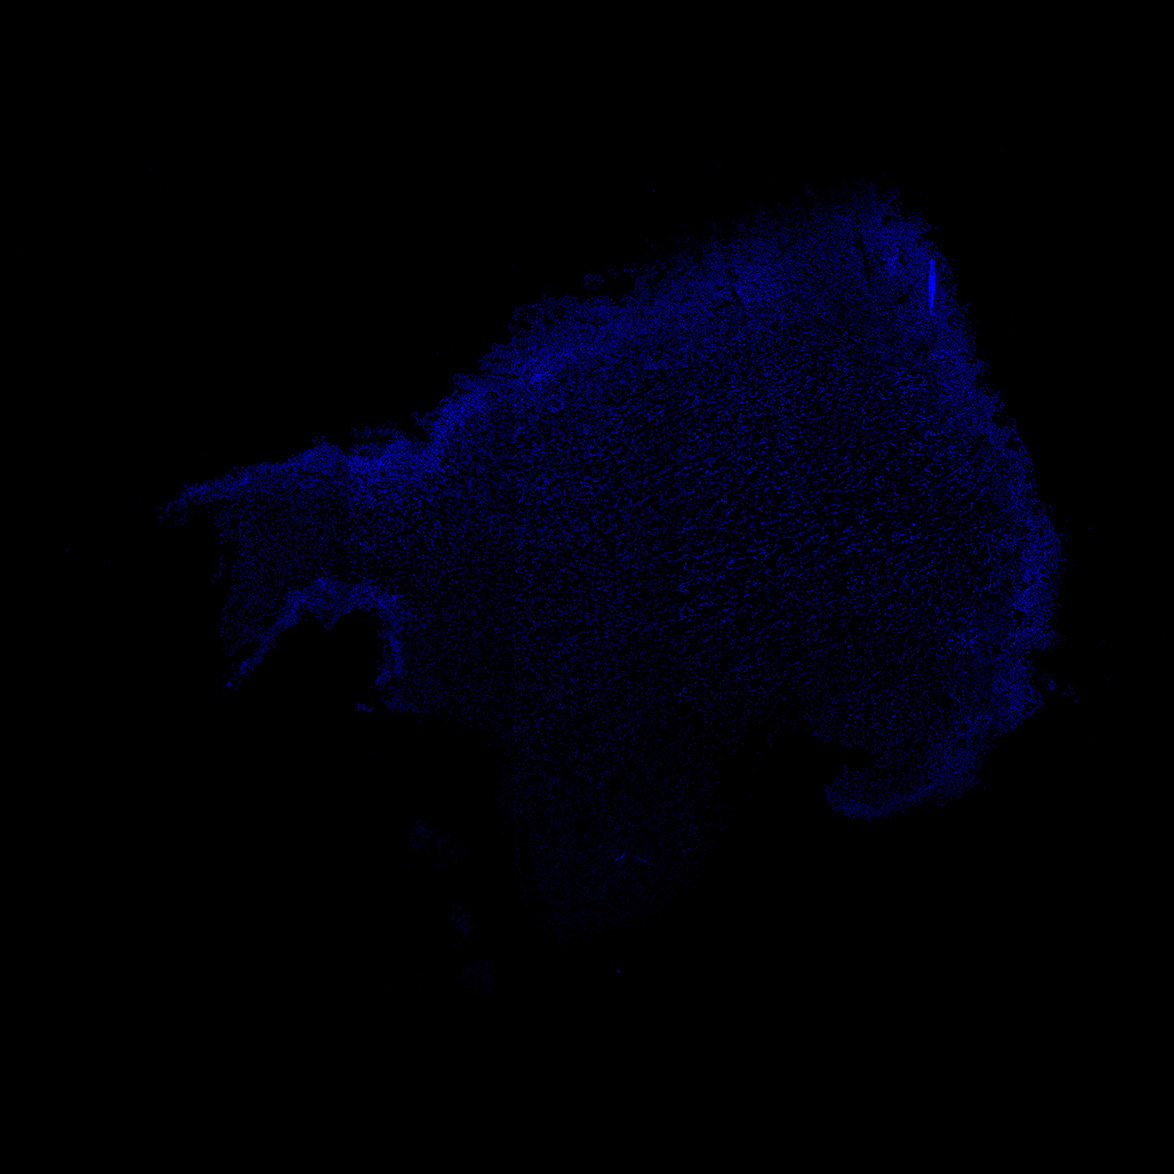

An anatomical analysis of the developing human midbrain from 6 post-conceptional weeks (PCW) to 22 PCW reveals increased tissue complexity, characterized by the emergence of dopaminergic nuclei, as highlighted by immunofluorescence analysis for tyrosine hydroxylase (TH).

22PCW

22PCW human midbrain